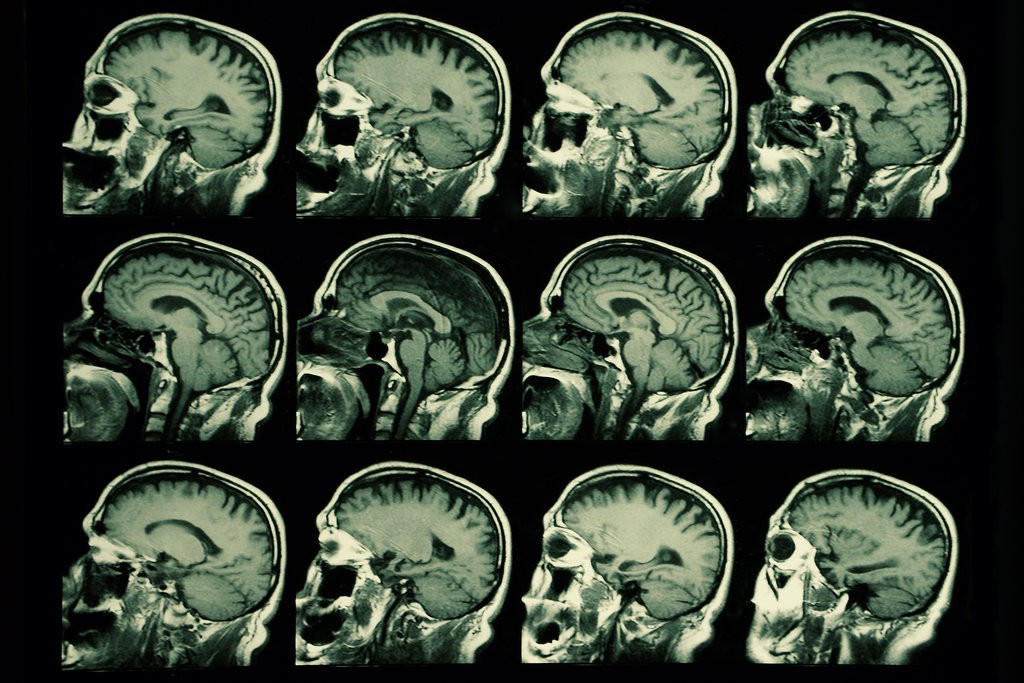

Trong một nghiên cứu mới, các nhà thần kinh học tại Đại học Boston đã mời hai nhóm đối tượng gồm thanh niên và những người ở độ tuổi 60-70 đến phòng thí nghiệm để đo các bước cơ bản về nhịp điệu thần kinh của họ. Họ đã thiết kế chương trình tACS để tối ưu hóa khớp nối nhịp nhàng giữa các khu vực vỏ não trước và thái dương trong mỗi bộ não cá nhân.